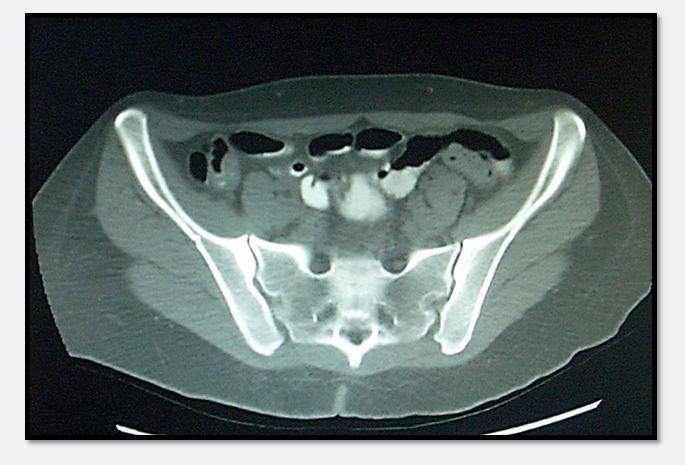

Figure 1.

Her urinalysis and pregnancy tests are normal and negative respectively. Her CBC shows a microcytic anemia with a hemoglobin of 9.1 g/dL and a white count that is elevated at 14.1. Liver enzymes and metabolic panel are both normal. A CT scan is ordered and shows mild colonic inflammation, especially in the area of the cecum, but a normal appendix. There is an additional clue on the image in Figure 1 above to the cause of the patient’s illness and whether it is infectious or inflammatory. Please click on image to enlarge

What is the CT finding and what is its significance?

Answer: Sclerosis of the sacroiliac joint, suggestive of inflammatory bowel disease